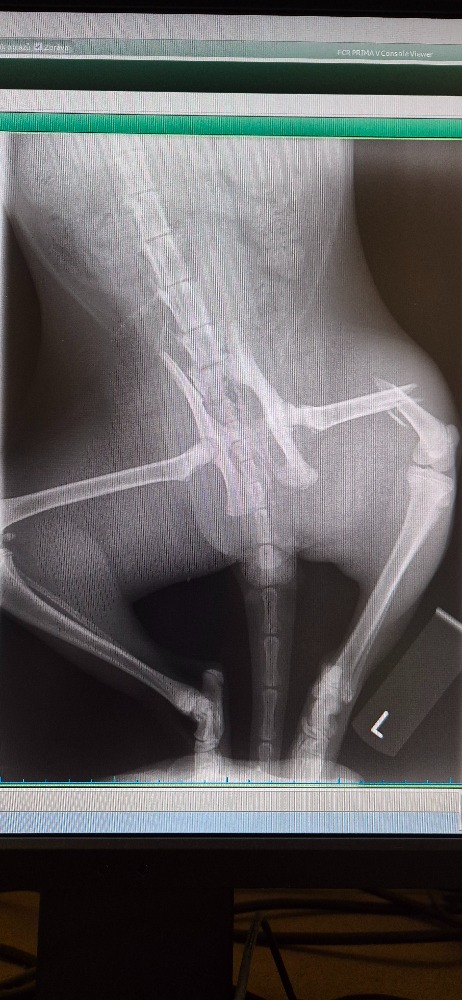

Shiva je odhadem asi dvouletý kocourek. Je velice přítulný a určitě musel žít s hodnými lidmi. Bohužel nyní je v kleci v útulku Kocour Felix a zotavuje se z těžké operace zadní nožičky. K nám do útulku se dostal 14. prosince, kdy jej našla na ulici před svým domem hodná paní. Z toho, jak se snažil plazit a marně stavět na nožičky jí bylo hned jasné, že musí být těžce zraněný. Zavolala tedy k nám, do Pražského spolu ochránců zvířat a na naši radu vzala kocourka na veterinu, kde mu udělali rentgen. Z něj bylo jasné, že má na dvakrát velmi ošklivě zlomenou nožičku a že samo se to rozhodně nezahojí. Dostal tedy léky proti bolesti a my jsme se neprodleně domluvili s vynikajícím ortopedem, který operuje ve veterinární klinice Fénix, že jej tam hned 17.12. bude operovat. Operace dopadla výborně a kocourek Shiva, jak jsme ho v útulku pojmenovali, bude po zahojení opět běhat. Je velice statečný a bolest i pobyt v kleci snáší báječně…